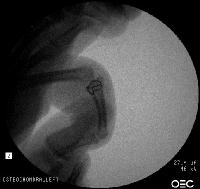

First impression was that the palmar fragment was probably big enough to take down and reinsert. However, comparison of films shortly after the fracture (above) and at two months (below) confirms the injury as a healed comminuted central impaction fracture with splay and hinging of the volar cortex.